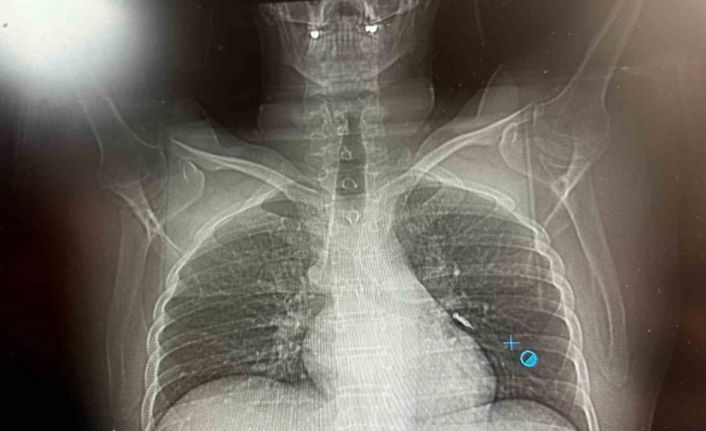

Konuya ilişkin konuşan Göğüs Cerrahi Op. Dr. Sadullah Aksoy, bir diş merkezinde diş tedavisi sırasında hastanın çenesine yerleştirilen implantın vida kısmının işlem esnasında yanlışlıkla aspire edildiğini belirtti. İlk olarak hastanenin ek hizmet binasında çekilen tomografi sonucunda, vidanın sol akciğerin hava yollarının yaklaşık dördüncü dalına kadar ilerlediği tespit edildiğini ifade eden Op. Dr. Aksoy, "Geçtiğimiz cumartesi günü öğle saatlerinde tarafımıza ulaşıldığında, hastanın Van Eğitim ve Araştırma Hastanesi’ne yönlendirilmesini istedik. Burada acil bronkoskopi planı yapılarak hasta kabul edildi. Hasta geldiğinde genel durumu iyiydi; solunumunu tamamen engelleyen bir bronş tıkanıklığı söz konusu değildi. Aynı gün hastamızı hazırladık. Bronkoskopi sırasında, implant vidasının sol üst lobun anterior segment bronşuna saplanmış pozisyonda olduğunu gördük. Üroloji bölümünde taş çıkarma işlemlerinde kullanılan cihazla müdahale ettik. İlk denemede implant tamamen çıkarılamadı ancak yerinden oynatılabildi. Bunun üzerine bir süre bekleyip hastayı yeniden bronkoskopi için hazırlamaya başladık. İşlem yaklaşık 3,5-4 saat sürdü ve saat 18.30 civarında hasta işlemden çıkarıldı" dedi.

Daha sonra hasta için yeniden bronkoskopi planladıklarını ancak bu süreçte hasta şiddetli bir öksürük geçirdiğini anlatan Aksoy, "Şiddetli öksürük sonrası yapılan kontrol akciğer filminde implant vidası görünmedi. Bunun üzerine toraks ve batın BT (bilgisayarlı tomografi) görüntülemesi istedik. Sonuçlarda implantın akciğerden çıktığı ve vücutta herhangi bir yerde bulunmadığı tespit edildi" diye konuştu.